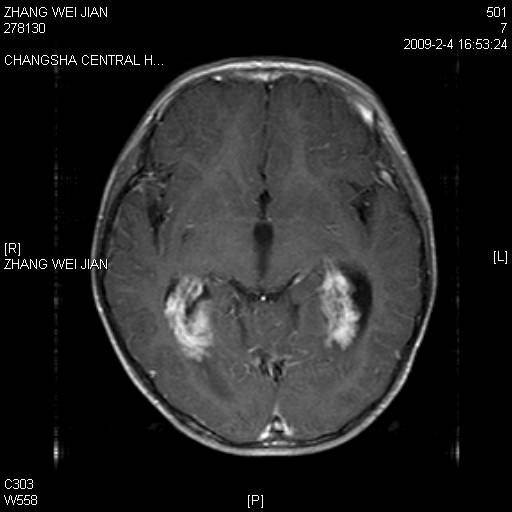

以下是引用guanaishengming在2009-2-6 22:51:00的发言:[br]脉络丛乳头状瘤

以下是引用随光逐影在2009-2-7 8:30:00的发言:[br]考虑双侧脑室脉络丛乳头状瘤并脑积水。

以下是引用同在2009-2-7 15:13:00的发言:[br]脉络丛乳头状瘤并脑积水。